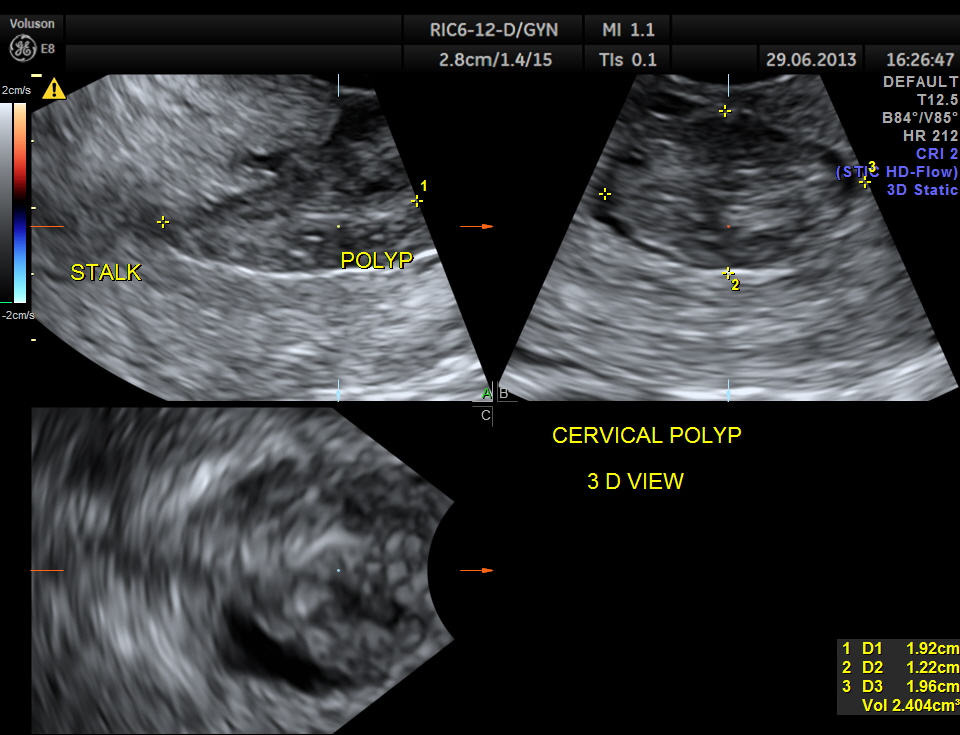

the multi planar 3 d image shows increased flow in the polyp and the stalk arising from the endometrium

The diagnosis offered was an endometrial polyp with a long stalk situated in the cervix.